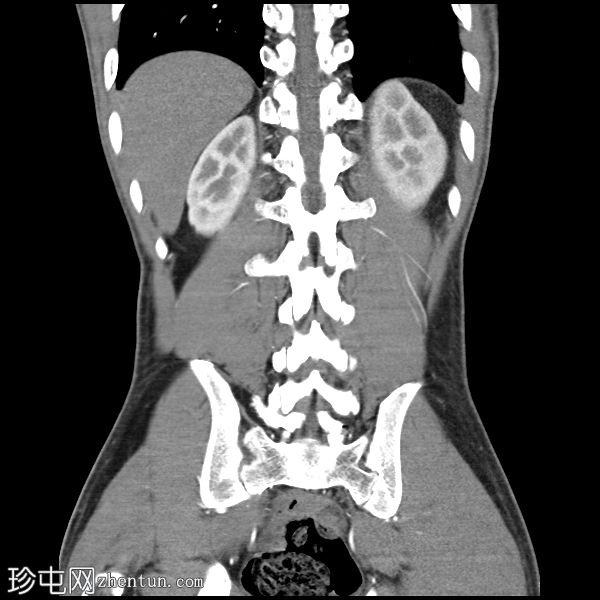

冠状位增强扫描

门静脉期

胰腺肿大。胰头、胰颈和胰体未见强化,边界不清且不规则。主胰管扩张,管内可见钙化。

胰腺实质内弥漫散在分布着大量钙化灶。

胰尾可见部分强化区域。

胰尾部钙化性假性囊肿。

影像学表现提示慢性钙化性胰腺炎伴胰尾部钙化性假性囊肿。

弥漫性实质及导管钙化是慢性钙化性胰腺炎的典型特征。

胰头及胰体无强化、形态不规则提示纤维化程度较重。

钙化性假性囊肿是一种慢性并发症,可通过囊壁钙化与肿瘤相鉴别。

CT是评估实质缺损、导管改变、钙化及假性囊肿的首选影像学检查方法。